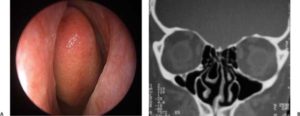

Причина возникновения большинства кист — закупорка протока слизистой железы из-за различных неблагоприятных причин. Чаще всего это происходит в результате воспалительной или аллергической реакции. Просвет железы закрывается, отделяемое не находит выхода и образуется пузырек, заполненный внутри жидким секретом. На фото вы видите, как выглядят кисты в носу:

Разновидности кист

Все кистозные образования в полости носа можно разделить на:

- Истинные;

- Ложные;

- Буллезные носовые раковины;

- Дермоидные кисты.

Истинные кисты образуются по описанному механизму: закупорка — накопление секрета — выпячивание слизистой. При этом стенкой кисты является слизистая оболочка полости носа. Она чаще всего растянута, лишена сосудов и нервов. Внутри кисты находится содержимое, по составу подобное секрету железы.

Ложные кисты имеют другую структуру, слизистая оболочка не участвует в образовании ее стенки. Ложной кистой, например, являются везикулезные элементы на слизистой носа при ветряной оспе.